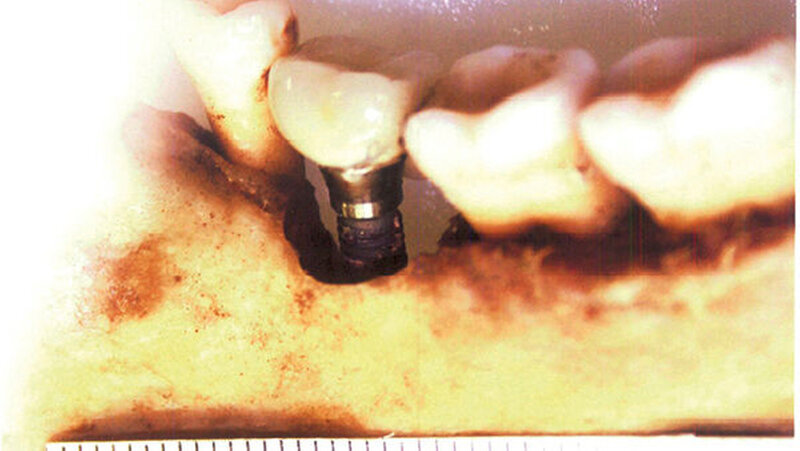

Zahnstatus:Aus dem Zahnstatus ersichtlich ist, dass es sich um hochwertige zahntechnische Arbeiten handelt, die auf eine mögliche privatkassenärztliche Versorgung schließen lassen. Der forensisch-odontologische Gutachter vermutet, dass alle Arbeiten durch denselben Zahnarzt gemacht wurden.

Neu:Inzwischen hat sich ergeben, dass es sich mit sehr hoher Wahrscheinlichkeit um XIFE-Implantate der Firma Densply Implants handelt.